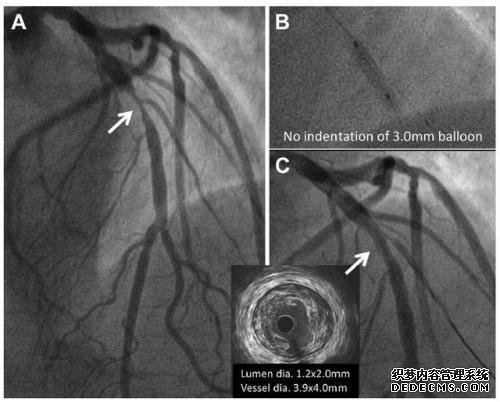

此时,示出了血管内造影剂导管的形状,使得造影剂导管仅钩住右冠状动脉,如图所示。

接下来,如下所示将管子穿过冠状造影剂(这种造影剂可能会在X射线下出现)。他们是右冠状动脉。

当使用造影剂时,右冠状动脉发育。如果不使用造影剂,则看不见血管。